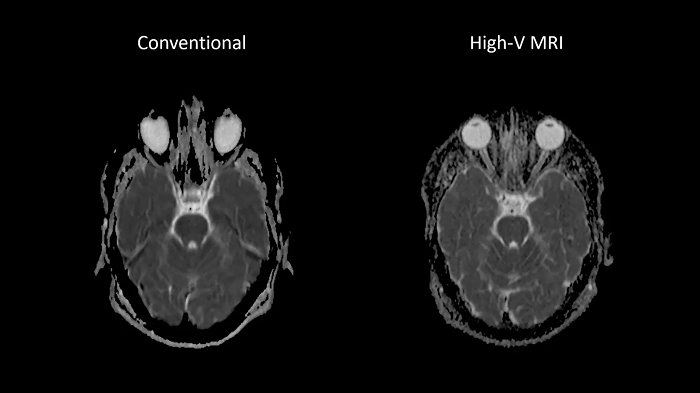

Reduced susceptibility challenges with High-V MRI

In MRI, susceptibility artifacts are a familiar phenomenon.

One notable example of such artifacts is at air-tissue interfaces, as they occur at the sinuses and orbits. The unique field strength of High-V MRI offers physical advantages that reduce susceptibility artifacts. This leads to reduced geometric distortions in diffusion imaging which results in improved diagnostic quality.

Image Courtesy: University Hospital Erlangen, Germany | Image-ID: 1aaaa3439 | 4aaaa0297